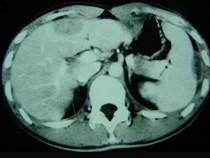

问题 男,35岁,病人低热、消瘦、乏力,左右季肋区疼痛,CT扫描如图,请选择最佳诊断()

选项 A.肝脓肿、腹腔脓肿 B.肝结核、腹腔结核 C.肝癌、腹腔转移 D.肝脏及腹腔转移瘤 E.肝海绵状血管瘤、腹腔脓肿

答案 B